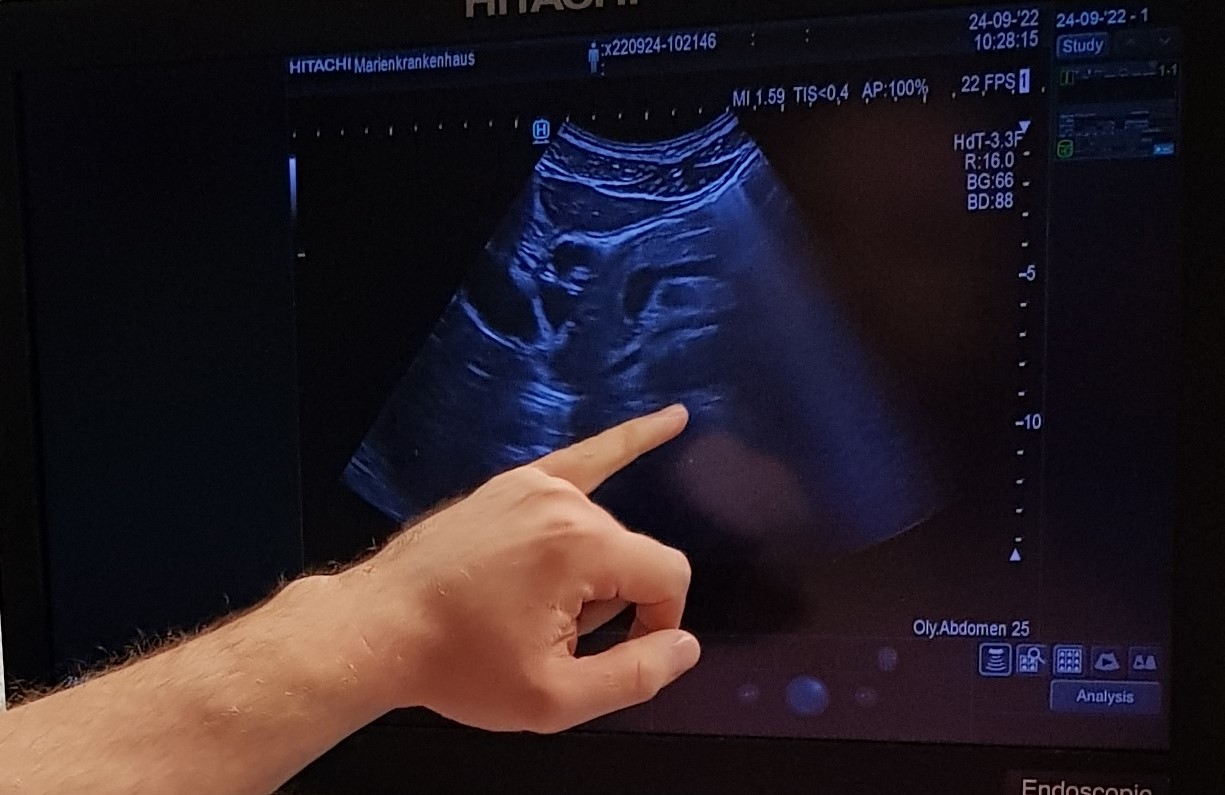

„Tief einatmen, Luft anhalten, Bauch rausstrecken.“ Ab jetzt wird es ernst für die jungen Ärzte der GFO Kliniken Rhein-Berg. Die Leber muss geschallt werden. „Lassen Sie sich Zeit, 30 bis 40 Minuten sind am Anfang völlig normal, wenn man die inneren Organe systematisch untersucht.“ Dr. Jamal Ali klärt auf: „Es gibt nicht die eine richtige Reihenfolge beim Schallen der inneren Organe. Finden Sie Ihren eigenen Untersuchungsgang.“

Beim Grundkurs Sonografie der GFO Kliniken Rhein-Berg, den der Oberarzt der Inneren Medizin initiiert und für die Assistenten am Vinzenz Pallotti Hospital Bensberg und im Marien-Krankenhaus Bergisch Gladbach durchgeführt hat, bekommt der Nachwuchs wichtige Tipps für den Klinikalltag.

Der Kurs ist Teil der strukturierten internistischen Ausbildung, die die Abteilung für innere Medizin anbietet. Leber, Gallensystem, Pankreas, Niere und Milz wurden am letzten Wochenende unter der Betreuung der gastroenterologischen Oberärzte Dres. Jamal Ali, Sebastian Weber, Ralf Nemitz und des Chefarztes Dr. Serhat Aymaz im MKH geschallt. Jedes Organ in zwei Ebenen – so wie es sich gehört.

Nachdem die Ärzte den Bauchraum gemustert und die Organe komplett „durchgefächert“ haben, müssen sie den Befund genau beschreiben, die entsprechenden Rückschlüsse ziehen und mögliche Artefakte, also Täuschungen, erkennen. Dabei ist es auch für die erfahrenen Untersucher gar nicht so einfach einen Gallenstein von einem Polypen zu unterscheiden. „Lassen Sie den Patienten aufstehen und hochspringen.“ Ist der Befund danach an einer anderen Stelle, sei es ein Stein. „Ein Polyp bewegt sich nicht.“